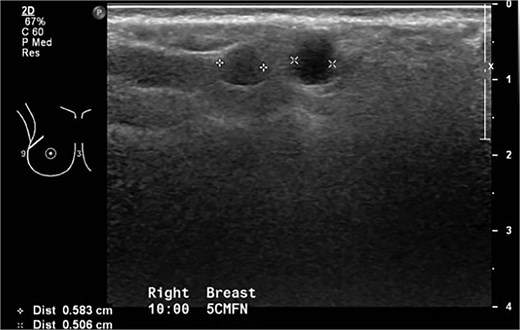

This was a 49-year-old lady of Philippine descent with previous free silicone injections in bilateral breasts in 1996. She was seen in the breast surgery clinic in October 2015 for a right breast lump in the upper outer quadrant. Mammogram showed extremely dense bilateral breasts with multiple dense oval opacities compatible with free silicone (Fig. 1). Ultrasound revealed a snowstorm appearance, with round cystic lesions scattered throughout both breasts representing silicone granuloma (Fig. 2). She was reassured at the time.

October 2015: Ultrasonography showing snowstorm appearance secondary to free silicone injection, with round cystic lesions scattered throughout both breasts representing silicone granuloma.